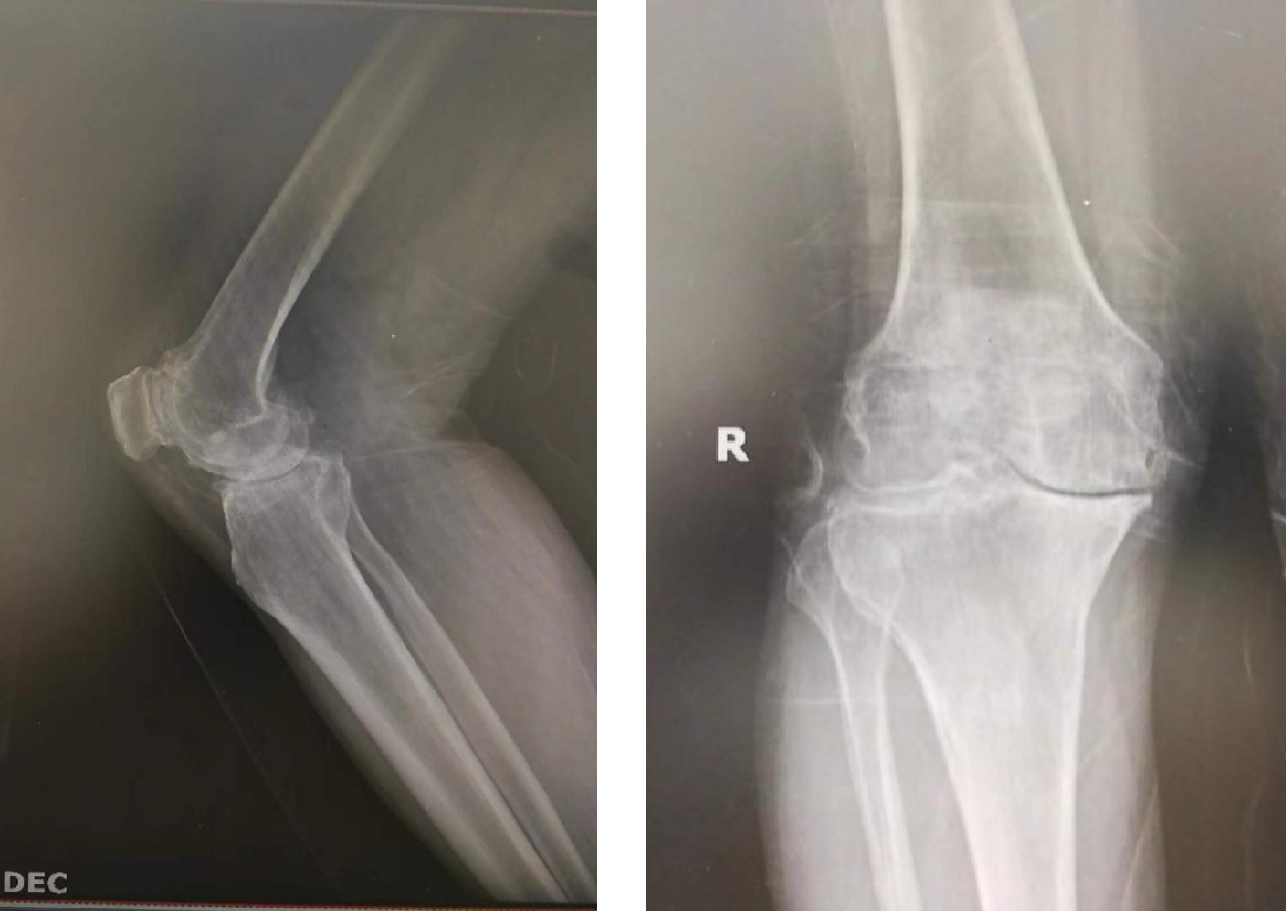

患者王某,男性,76岁,右膝关节骨性关节炎(重度)6年,因经济原因,老人一直承受着膝关节疼痛、屈伸活动受限的痛苦。之前慕名来我院找赵明祥主任计划行膝关节置换,赵明祥主任了解病情及患者经济能力后,告知患者人工髋膝关节假体很快实行集采政策,假体价格会大幅度下调,到时候患者既能少花钱又能取得一样的治疗效果。患者得知消息后非常激动。集采价格实施后,赵明祥主任立即通知患者,并于5月9日成功给患者实施了右膝关节置换术。